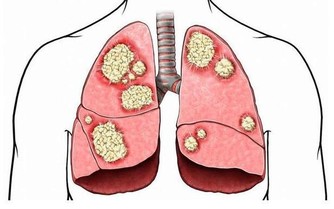

在臨床上,是沒有慢性結腸炎這個診斷的,因為它是一系列可以引起腸道炎性水腫、出血、潰瘍及功能紊亂疾病的總稱。這個總稱可以叫做炎症性腸病,而慢性結腸炎就是發病部位在結直腸的炎症性腸病。潰瘍性結腸炎為炎症性腸病中發病部位於結直腸的疾病,但是很多慢性結腸炎的患者並沒有潰瘍型結腸炎的腸鏡特徵。所以慢性結腸炎並不僅僅包括潰瘍性結腸炎。